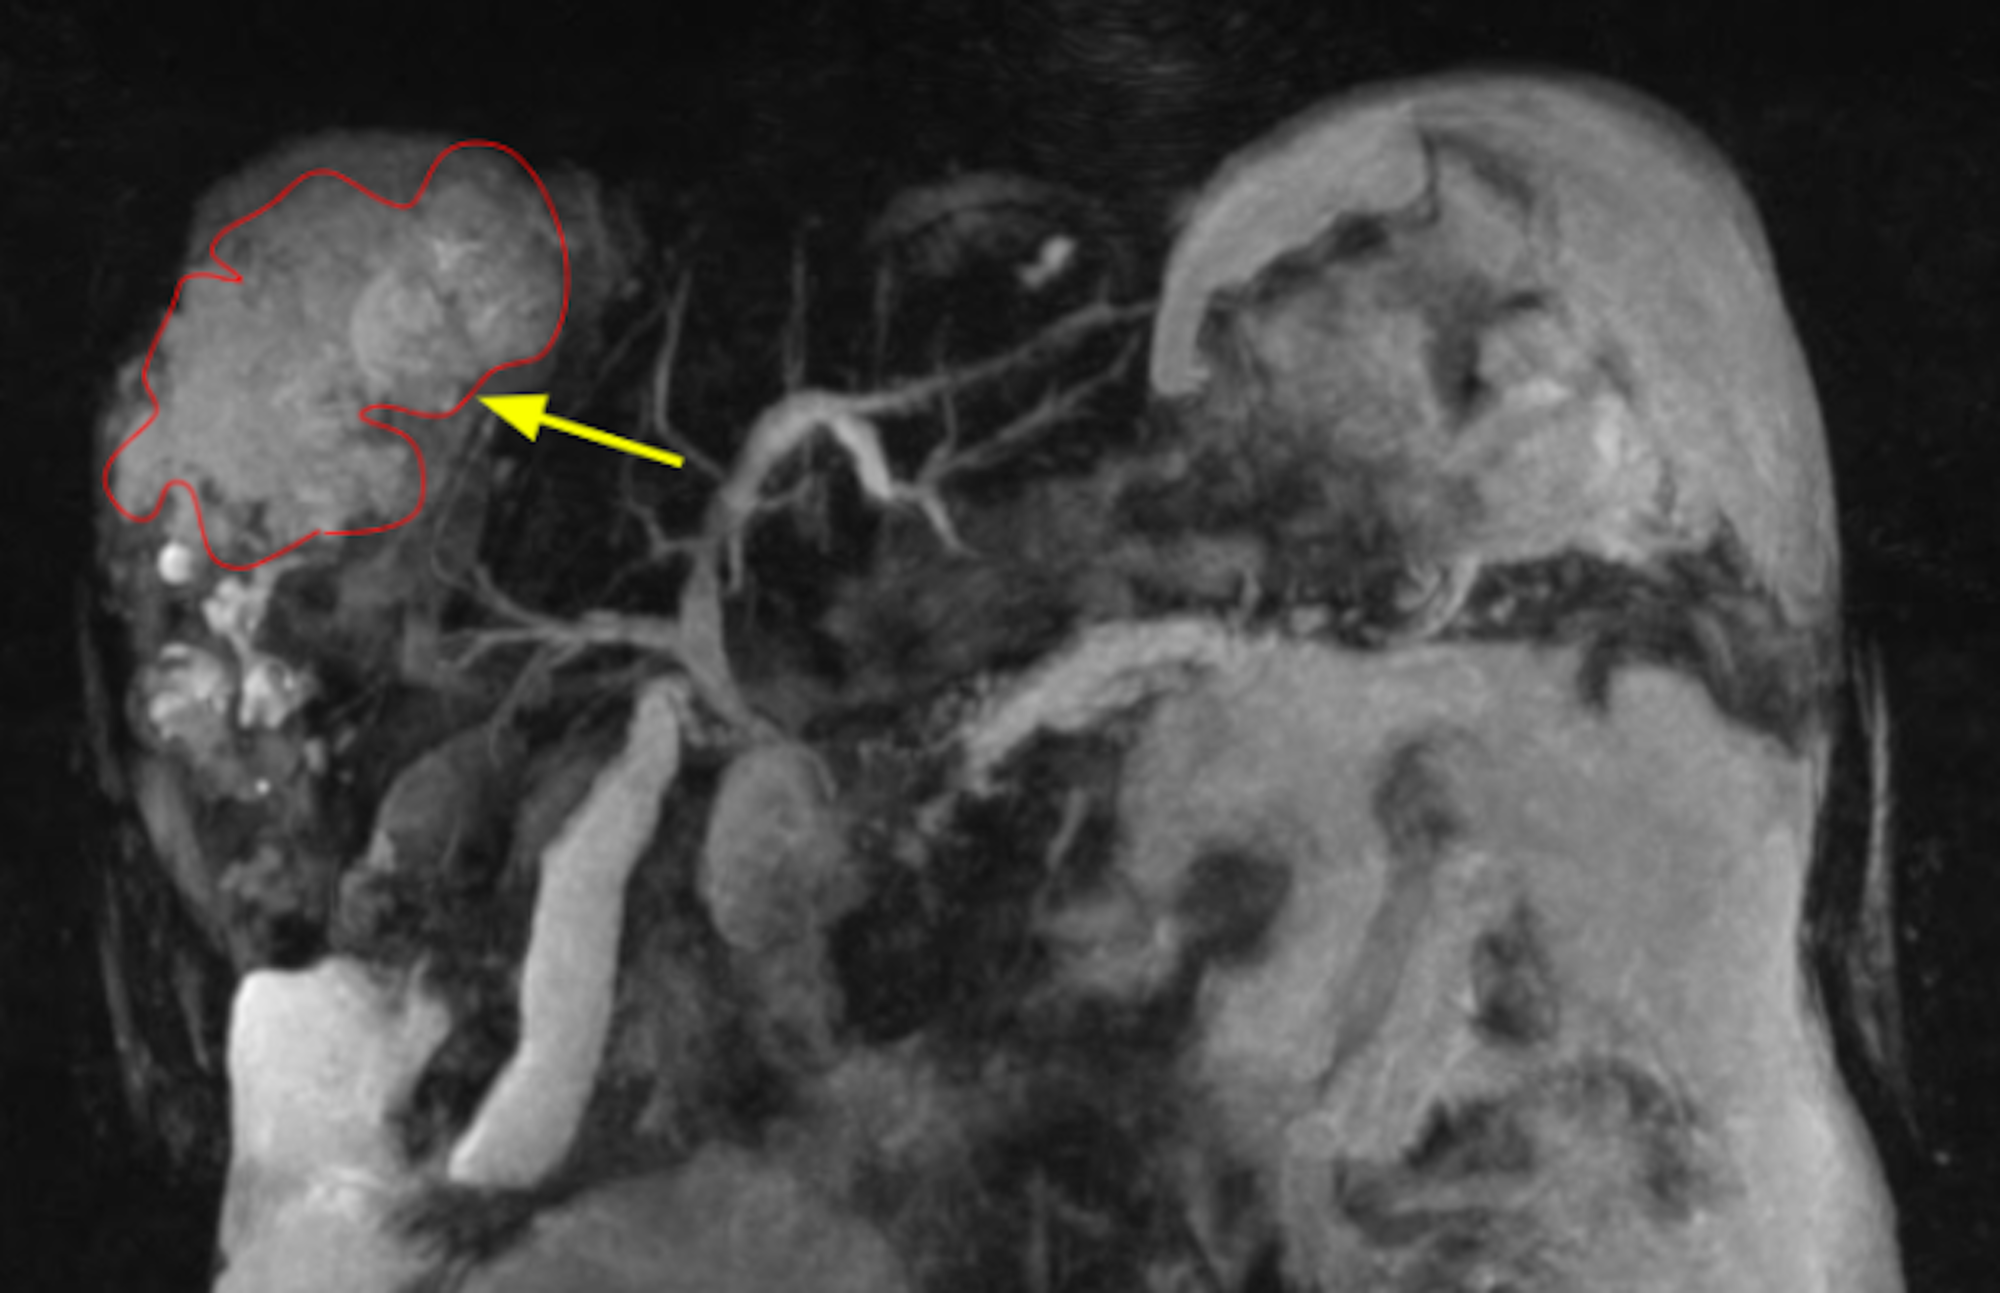

From www.ajronline.org

Biloma Formation After Radiofrequency Ablation of Hepatocellular Radiology Biloma Biloma a biloma is an intra‐ or extrahepatic bile collection secondary to a gb or biliary duct leak. Alternatively, a biloma may be. As clinical signs and symptoms of bilomas are often nonspecific and laboratory values may be unremarkable, imaging modalities including. After pigtail drainage (under ct. Management varies depending on the clinical presentation, laboratory results, and radiological findings of. Radiology Biloma.

Biloma Formation After Radiofrequency Ablation of Hepatocellular Radiology Biloma The goals of imaging in the assessment of biloma are: After pigtail drainage (under ct. Biloma a biloma is an intra‐ or extrahepatic bile collection secondary to a gb or biliary duct leak. As clinical signs and symptoms of bilomas are often nonspecific and laboratory values may be unremarkable, imaging modalities including. Alternatively, a biloma may be. Confirm the presence. Radiology Biloma.